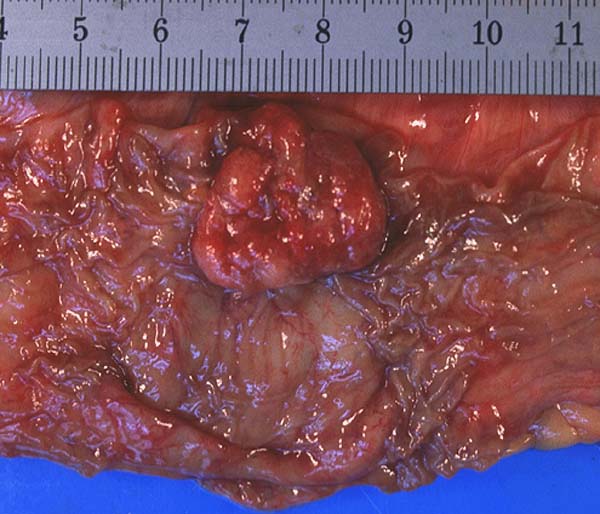

PathoPic ID 508 - Adenom

Adenom

Kolon

Polypoider Tumor im Kolon.

Zufallsbefund bei Autopsie.

Makroskopie